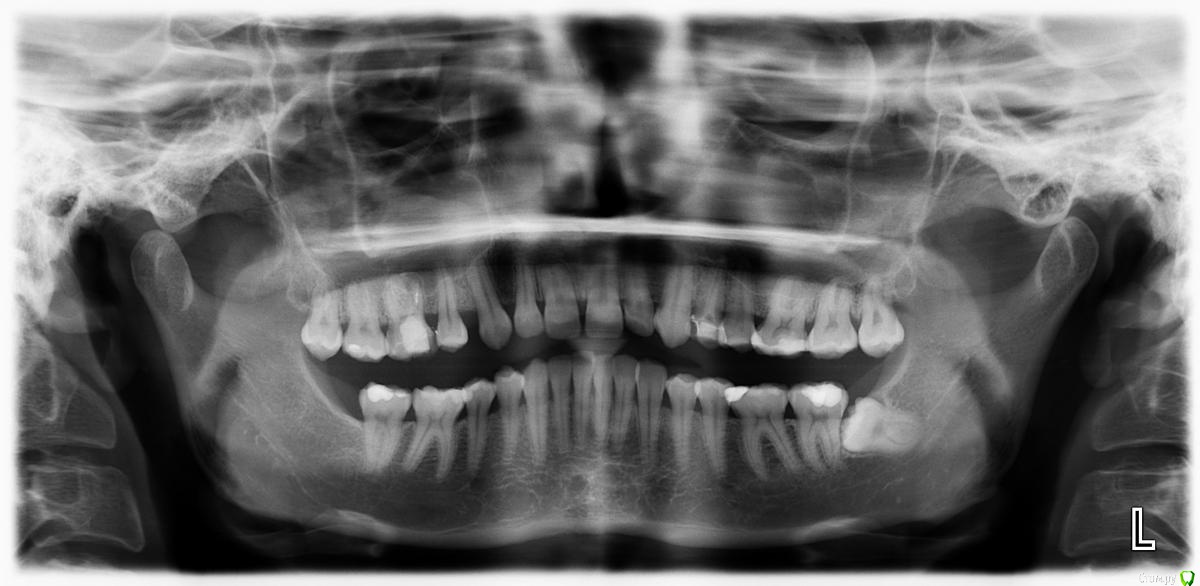

losenok83 Опубликовано 11 мая, 2016 Поделиться Опубликовано 11 мая, 2016 Здравствуйте! Мне 32 года. Год в брекетах. Уже больше 3-х месяцев беспокоит боль в в суставе, при открывании рта, иногда при жевании. До брекетов у меня хрустел сустав с левой стороны, сейчас хрустит с обеих сторон+ закладывает периодически уши. Лечусь с удалением 4-рок на ВЧ. Справа 4-ка была удалена в детстве по орт.показаниям , слева вначале нынешнего лечения. Не связана ли боль в суставе с удалением 4-рок? Действительно ли нужно было их удалять? Не нужно ли было выдвигать нижнюю челюсть вперед спец. аппаратами? И что можно сделать сейчас? Фото и снимки до лечения. Ретинированная 8-ка удалена. Ссылка на комментарий

losenok83 Опубликовано 4 сентября, 2016 Автор Поделиться Опубликовано 4 сентября, 2016 Здравствуйте, очень нужна ваша помощь снова! Я обошла много ортодонтов в своем городе на предмет дальнейшего лечения. В конце концов мое самочувствие более менее менее улучшилось только после ортотика. В дальнейшем мне сказали ортодонт поставит мои зубы на такую высоту. Скажите пожалуйста это правда возможно, на такую высоту вытянуть свои верхние и нижние зубы? И еще изначально этот ортодонт планировала что в этом ортотике Н,Ч, выйдет вперед , а потом ее расширят. Поскольку этого не произошло, сказала что просто раздвинут место для раннее удаленных 4-рок на В,Ч. пружинами. А я очень боюсь, что в результате зубы будут торчать вперед как раньше.Разве нет? Расчет ТРГ на данный момент лечения. И вид челюстей в ортотике. Ссылка на комментарий